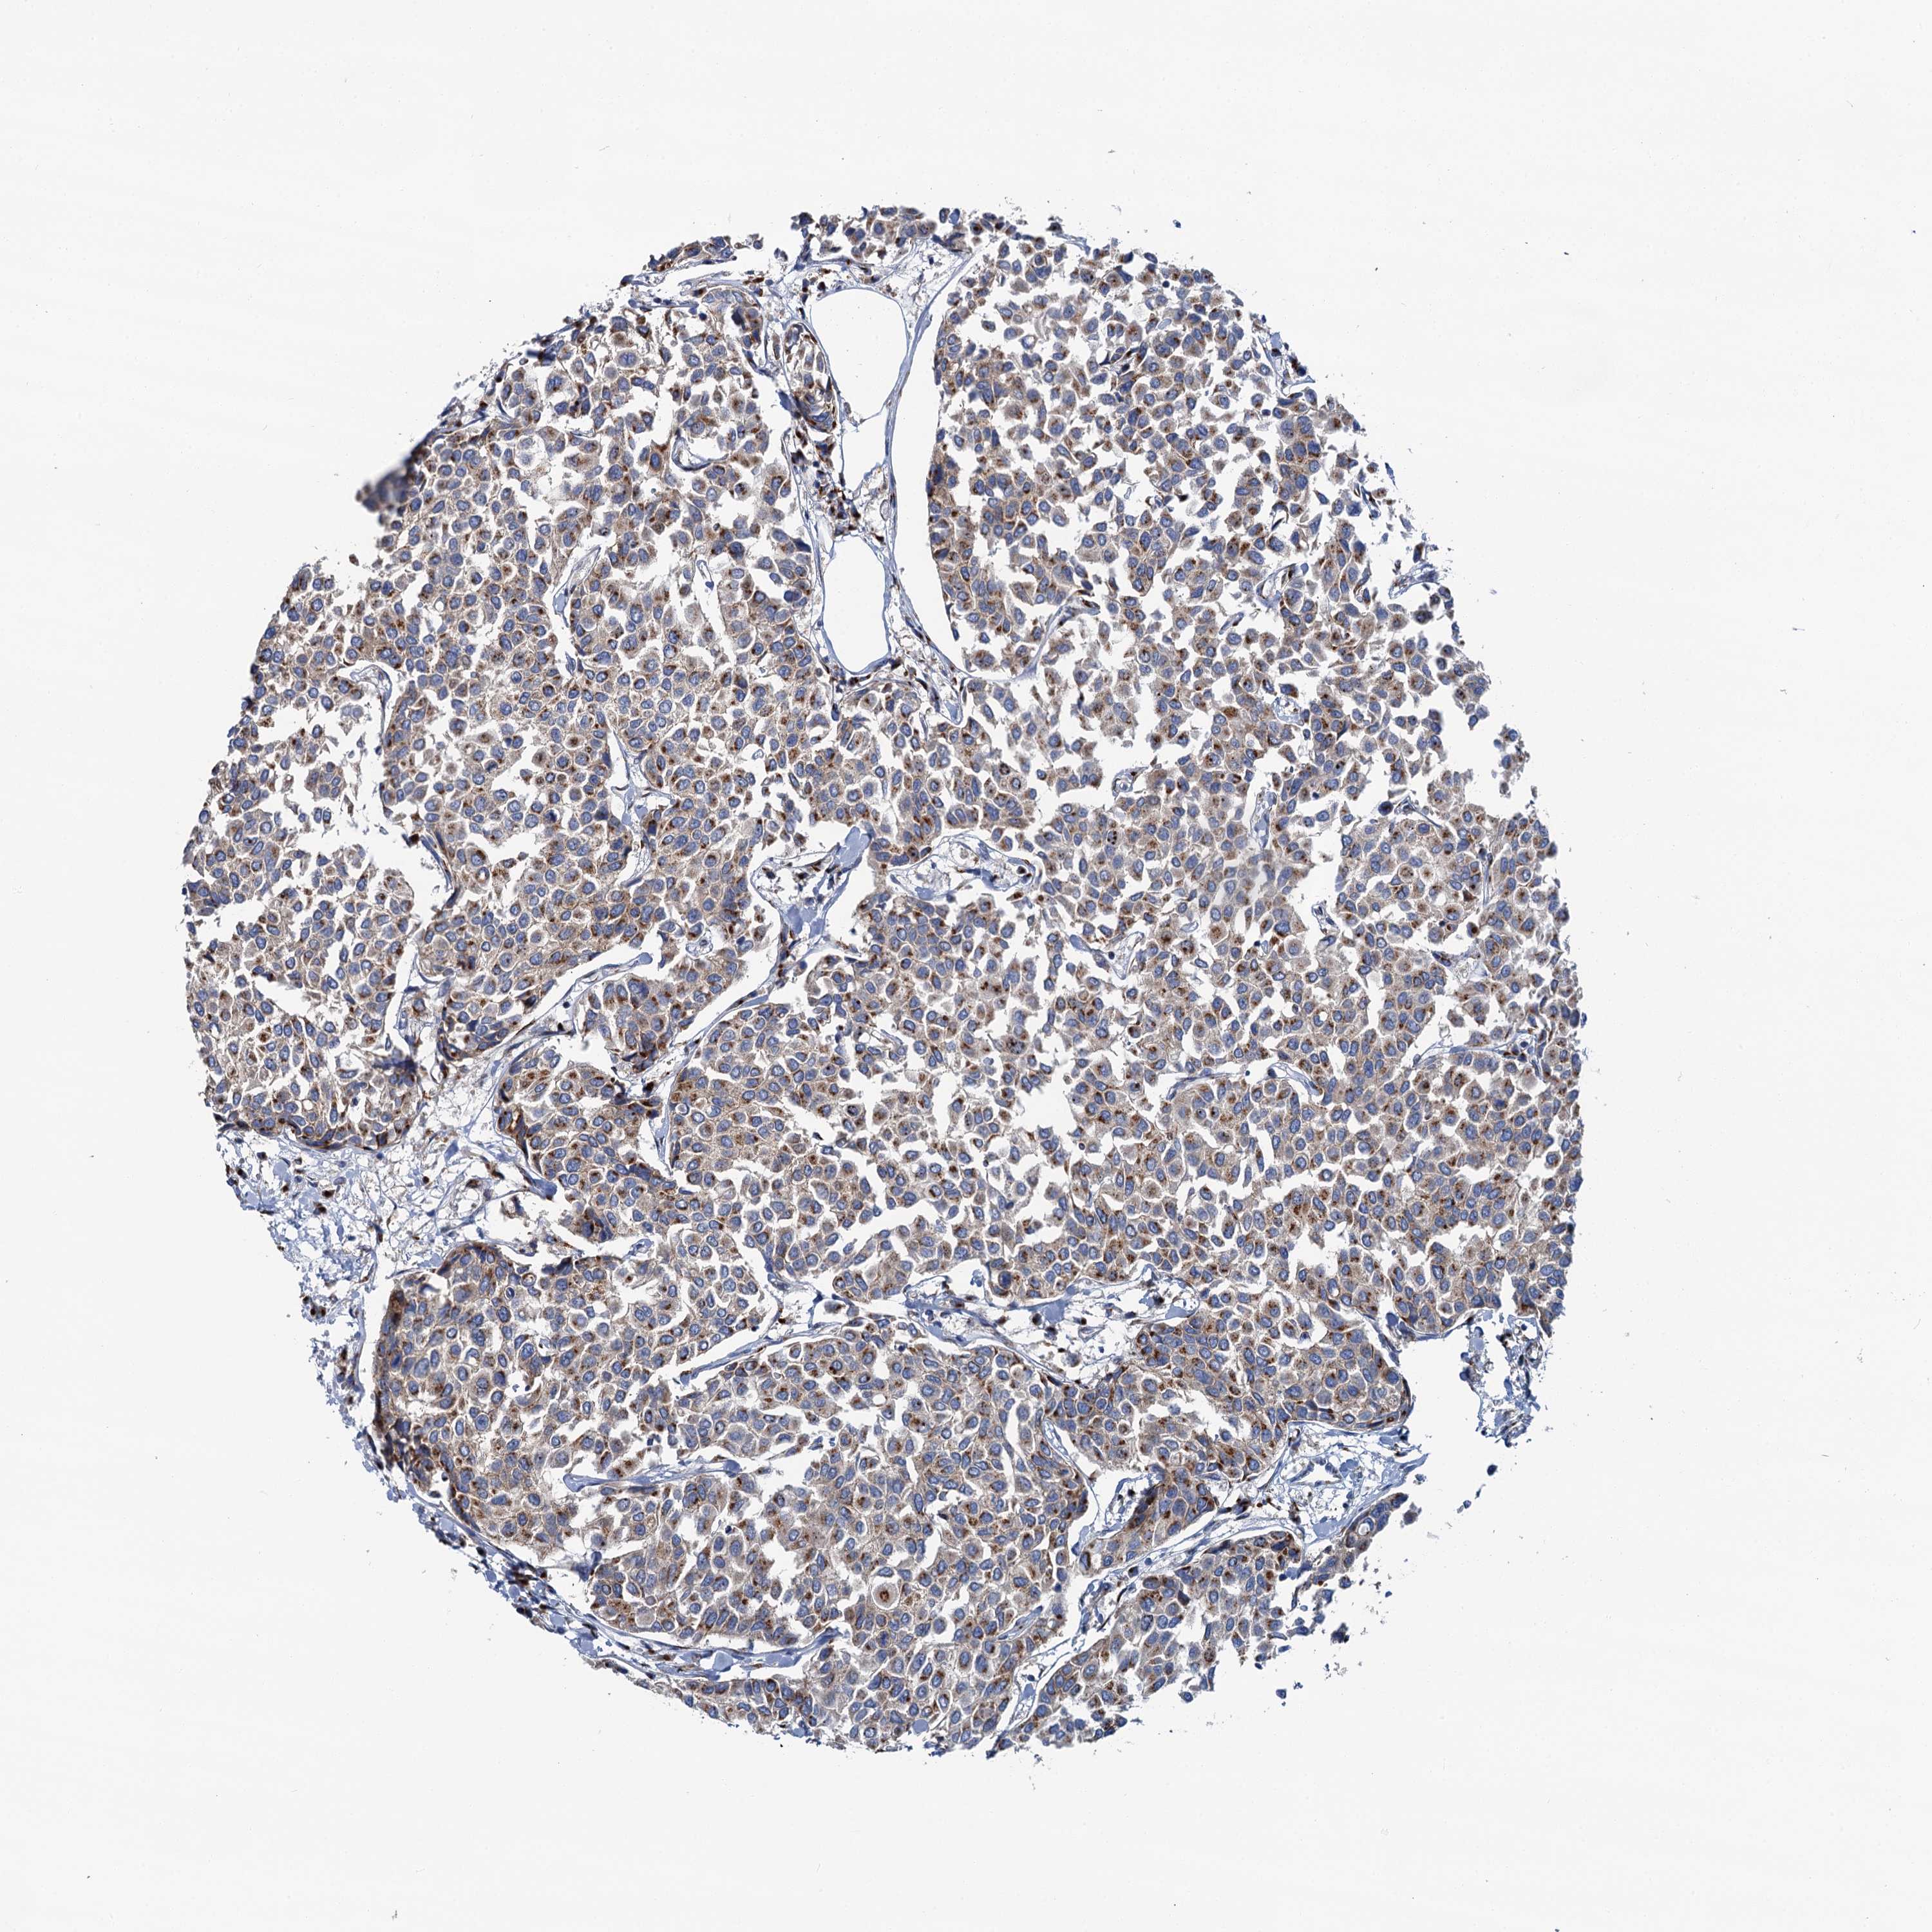

BRCA TCGA BRCA VALIDATION PROTEIN EXPRESSION